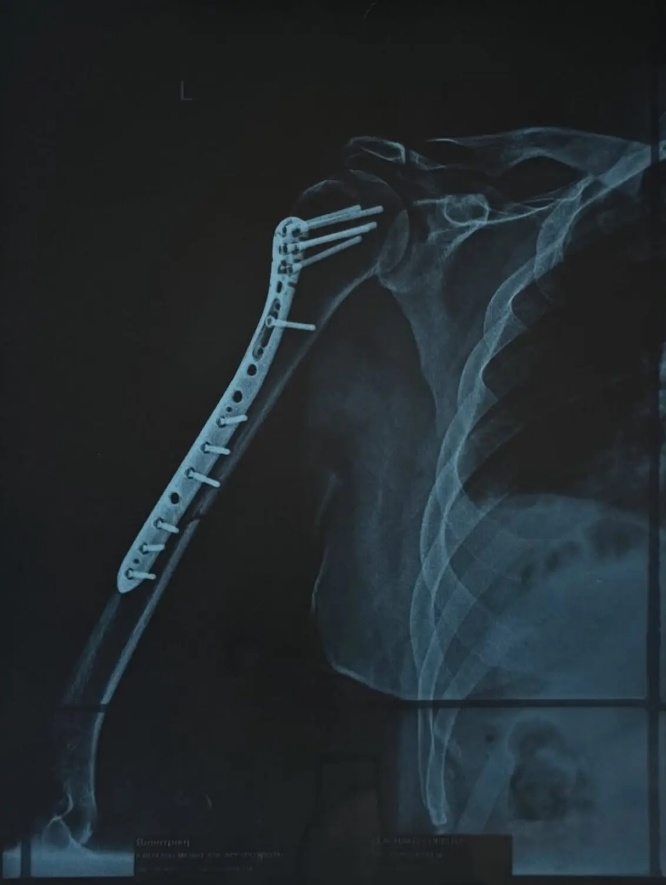

«Φίλοι μου, θέλω να σας ευχαριστήσω μέσα από την καρδιά μου για τα μηνύματα και την αγάπη που μου στέλνετε αυτές τις μέρες. Δυστυχώς η αποκατάσταση του χεριού μου θα πάρει περισσότερο χρόνο από όσο υπολογίζαμε. Το κάταγμα ήταν πολύ σοβαρό και το χειρουργείο ακόμη πιο απαιτητικό, οπότε οι γιατροί μου συνέστησαν να μείνω εκτός εμφανίσεων για λίγο διάστημα.

Δύσκολες στιγμές περνά τον τελευταίο καιρό ο Χρήστος Δάντης, καθώς υπέστη κάταγμα στο χέρι και χρειάστηκε να υποβληθεί σε χειρουργική επέμβαση. Ο γνωστός τραγουδιστής και συνθέτης μεταφέρθηκε στην Ευρωκλινική Αθηνών πριν από μία εβδομάδα, με την κατάσταση του χεριού του να είναι ιδιαίτερα επιβαρυμένη, όπως περιέγραψε ο ίδιος.

Μέσα από ανάρτησή του, ο τραγουδιστής θέλησε να ευχαριστήσει δημόσια τον γιατρό που τον χειρούργησε, περιγράφοντας τη δύσκολη κατάσταση στην οποία βρέθηκε πριν μπει στο χειρουργείο: «Όταν θυμάμαι σε ποια κατάσταση μπήκα στην Ευρωκλινική Αθηνών το βράδυ της Πέμπτης, με το χέρι σχεδόν διαλυμένο και σκέφτομαι πόσο γρήγορα θα ανέβω ξανά στη σκηνή την Παρασκευή που έρχεται… μόνο ευγνωμοσύνη μπορώ να νιώσω.

Το «τεράστιο ευχαριστώ» ανήκει στον Χειρουργό Γιώργο Μάζη @shoulderexpert και σε όλο το επιτελείο του, αν και είναι λίγο μπροστά σε αυτό που έκαναν για μένα. Με χειρούργησαν και μου «έδωσαν» πίσω το χέρι μου και τη δυνατότητα να επιστρέψω εκεί που ανήκω: στη σκηνή!», έγραψε στην ανάρτησή του ο Χρήστος Δάντης.